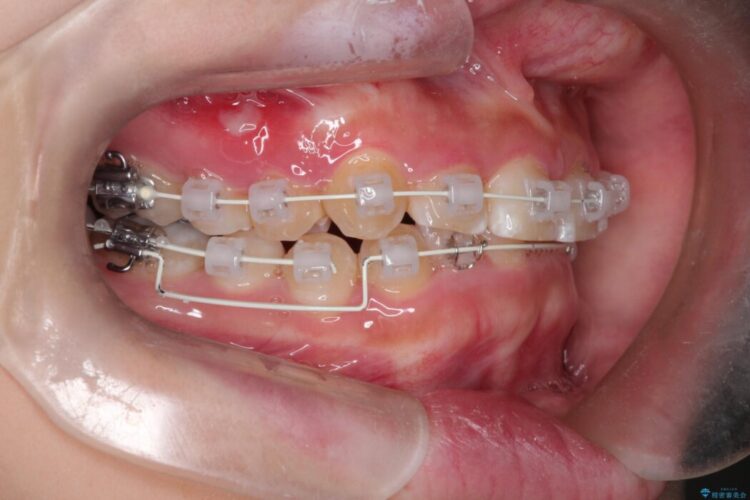

- 矯正装置:審美装置

本書例では下顎前歯を圧下させ、突出してしまっている臼歯部の挺出を戻す計画としました。

ワイヤー装置は患者様の希望からあまり目立ちにくい白い審美装置を使用しています。